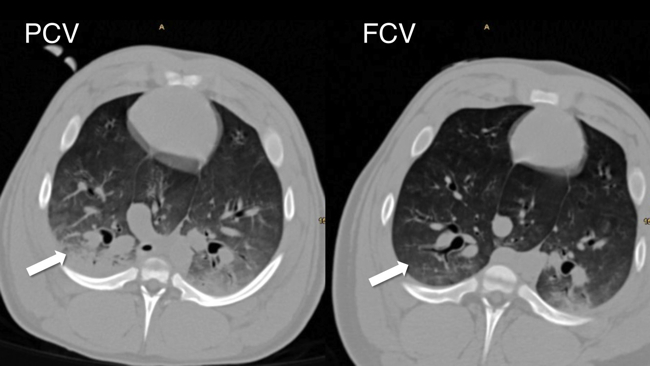

Patrick Spraider, Julia Abram, Gabriel Putzer, Lisa Schnegg, Judith Martini

Our group investigates flow-controlled ventilation (FCV) as a novel ventilation method established to guarantee a continuous, constant and typically identical flow during inspiration and expiration. Additionally, the constant flow coupled with direct intratracheal pressure measurement allows accurate evaluation of dynamic compliance and adjustment of ventilation settings accordingly. Our first experimental pilot study demonstrated more efficient gas exchange and improved oxygenation as well as less atelectasis in individualised FCV compared with pressure-controlled ventilation (PCV) at the best standard of care during long term ventilation. Similar results were observed in an experimental model of single lung ventilation and in an experimental model of acute respiratory distress syndrome. Two clinical ventilation studies are currently being conducted in patients undergoing cardiac surgery and thoracic surgery with single lung ventilation, comparing individualised FCV with standard-of-care PCV.

- Spraider, P.; Martini, J.; Abram, J.; Putzer, G.; Glodny, B.; Hell, T.; Barnes, T.; Enk, D.: Individualized flow-controlled ventilation compared to best clinical practice pressure-controlled ventilation: a prospective randomized porcine study. CRITICAL CARE. 2020; 24(1): 662.

- Enk, D.; Spraider, P.; Abram, J.; Barnes, T.: Pressure Measurements in Flow-Controlled Ventilation. CIRTICAL CARE MEDICINE. 2020; 48(12): e1359-e1360.